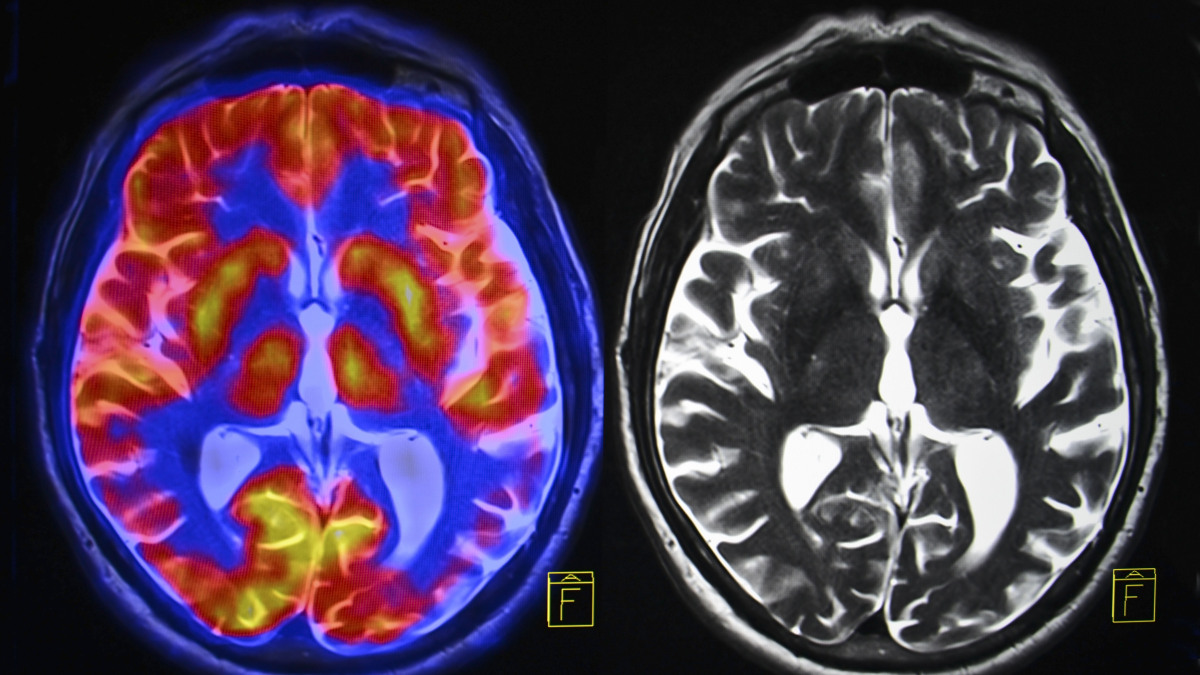

MADRID – Las complicaciones

neurológicas de la covid-19 pueden incluir delirio, daño nervioso, derrames y

un raro tipo de inflamación cerebral, aunque los investigadores no tienen

claro, en este último caso, si es producto del coronavirus o de la reacción

inmunitaria, según un estudio que publica la revista Brain.

Según la investigación,

“parece” que, debido a la pandemia, está aumentando la prevalencia de

una “rara y a veces mortal” afección inflamatoria, la

encefalomielitis diseminada aguda (ADEM), indica un comunicado del UCL.

De entre todos los pacientes,

doce presentaron inflamación cerebral y, de ellos, nueve sufrieron ADEM, una

afección que normalmente se ve en niños y que puede desencadenarse por

infecciones virales.

El SARS-Cov-2 no fue detectado

en el líquido cefalorraquídeo de ninguno de los pacientes del estudio, lo que

“sugiere que el virus no atacó directamente al cerebro para causar la

enfermedad neurológica”, indica a nota.

Pero en algunos pacientes, sí

encontraron pruebas de que la inflamación del cerebro estaba

“probablemente causada” por una respuesta inmunológica a la

enfermedad, lo que “sugiere que algunas complicaciones neurológicas de la

covid-19 podrían provenir de la respuesta inmunológica, más que del propio virus”.